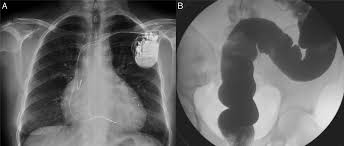

Eventos farmacológicos adversos y factores asociados en pacientes con enfermedad de Chagas crónica

Rev Soc Bras Med Trop. 22 de abril de 2020. Las etapas avanzadas de la enfermedad cardíaca de Chagas y la edad tienen una asociación significativa con la presencia de RAMs. Además, se identificó la tos como el principal evento adverso observado con frecuencia de los inhibidores de la ECA.